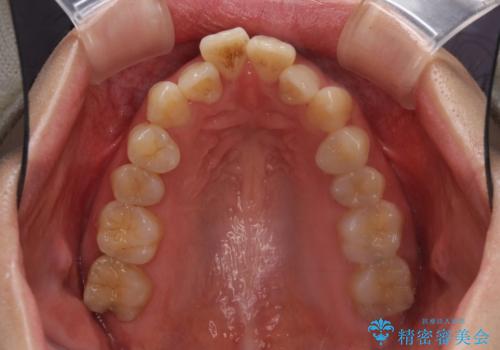

Eラインを改善したい ハーフリンガルによる抜歯矯正

- 口元の突出感を気にして来院された患者様です。

上下左右の第一小臼歯4本を抜歯して口元を下げる治療計画としました。

舌の突出癖が強く、口元を引っ込める力に拮抗してしまい、抜歯スペースを閉じるまでに時間がかかりました。

また途中出産もありましたが、無事に治療を終えることができました。